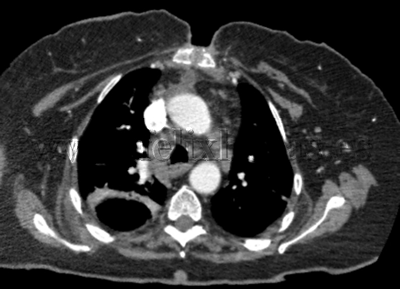

Mediastinitis anterior post esternotomía